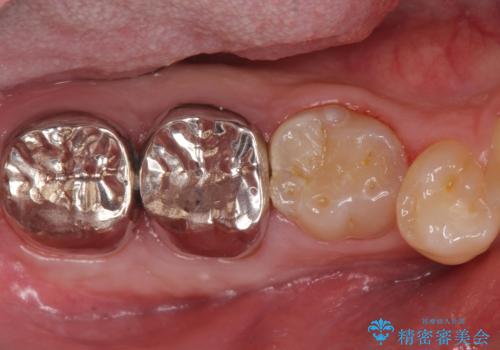

- 口の中を予算の範囲内でできるだけきれいにしたいとのことで来院された患者様です。

矯正治療と虫歯治療を組み合わせてご提案しましたが、ご予算との兼ね合いで虫歯治療のみを行うこととなりました。

奥歯は十分な歯の高さがなかったため、クラウンをかぶせる前に歯周外科治療で歯の高さを出しています。

歯科に通うようになってから磨き残しの状態も改善されていきました。